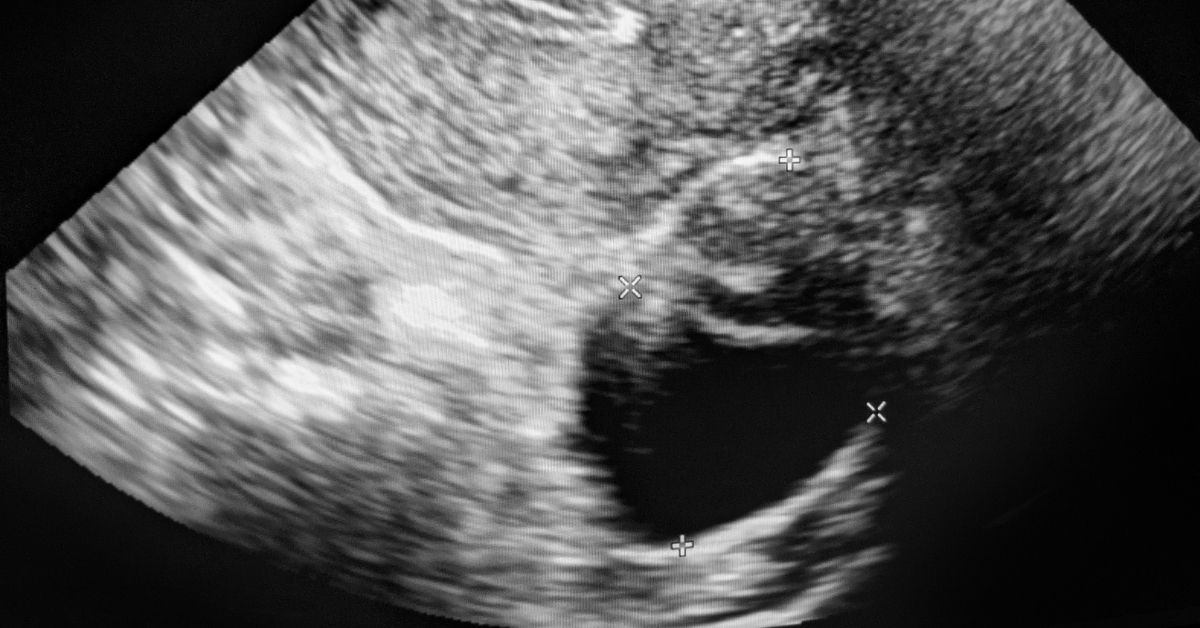

Jinekolojik kanserler içinde tespiti en zor olan ve ne yazık ki en ölümcül seyredebilen türdür. Çünkü yumurtalıklar karın içinde geniş bir boşlukta yer alır ve tümör büyüyene kadar çevre organlara baskı yapmaz. Bu nedenle rutin kontroller hayati önem taşır.

Hayır, göstermez. Bu çok yaygın bir yanlıştır. Smear testi sadece rahim ağzı (serviks) kanserini ve öncülerini tarar. Rahim içini veya yumurtalıkları göstermez. Yumurtalık kanseri için yıllık ultrason muayenesi ve gerekirse tümör belirteçleri (Ca-125) kontrolü gerekir.